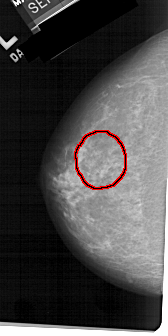

A_1224_1.LEFT_MLO

FILE: A_1224_1.LEFT_MLO.OVERLAY

TOTAL_ABNORMALITIES 1

ABNORMALITY 1

LESION_TYPE MASS SHAPE IRREGULAR MARGINS SPICULATED

ASSESSMENT 4

SUBTLETY 3

PATHOLOGY MALIGNANT

TOTAL_OUTLINES 1

BOUNDARY